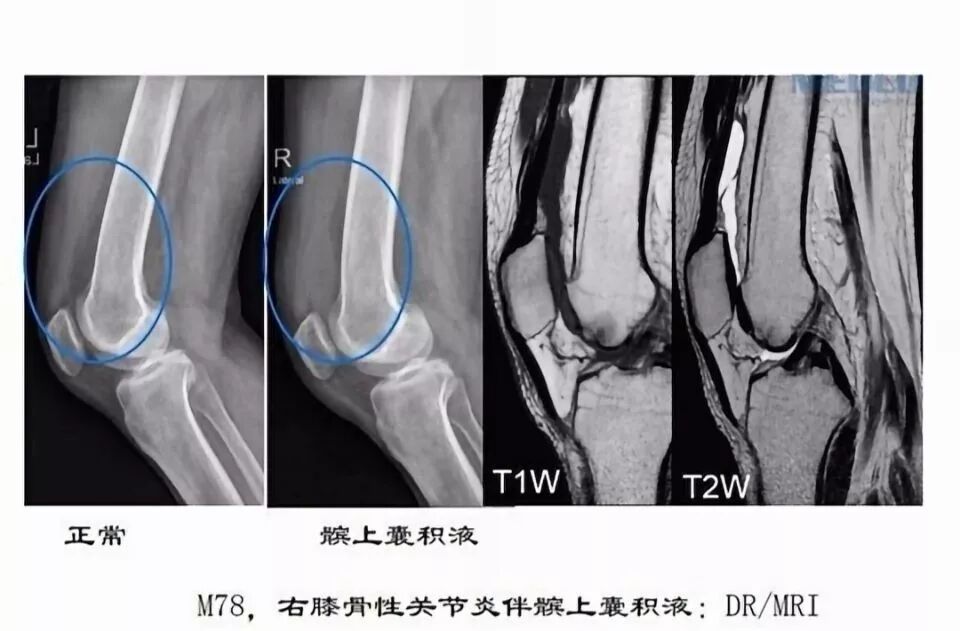

滑囊是关节囊外的囊性结构,可与关节囊相通,其作用是减少肌腱、骨和皮肤之间的摩擦。可以分为先天性滑囊和获得性滑囊。